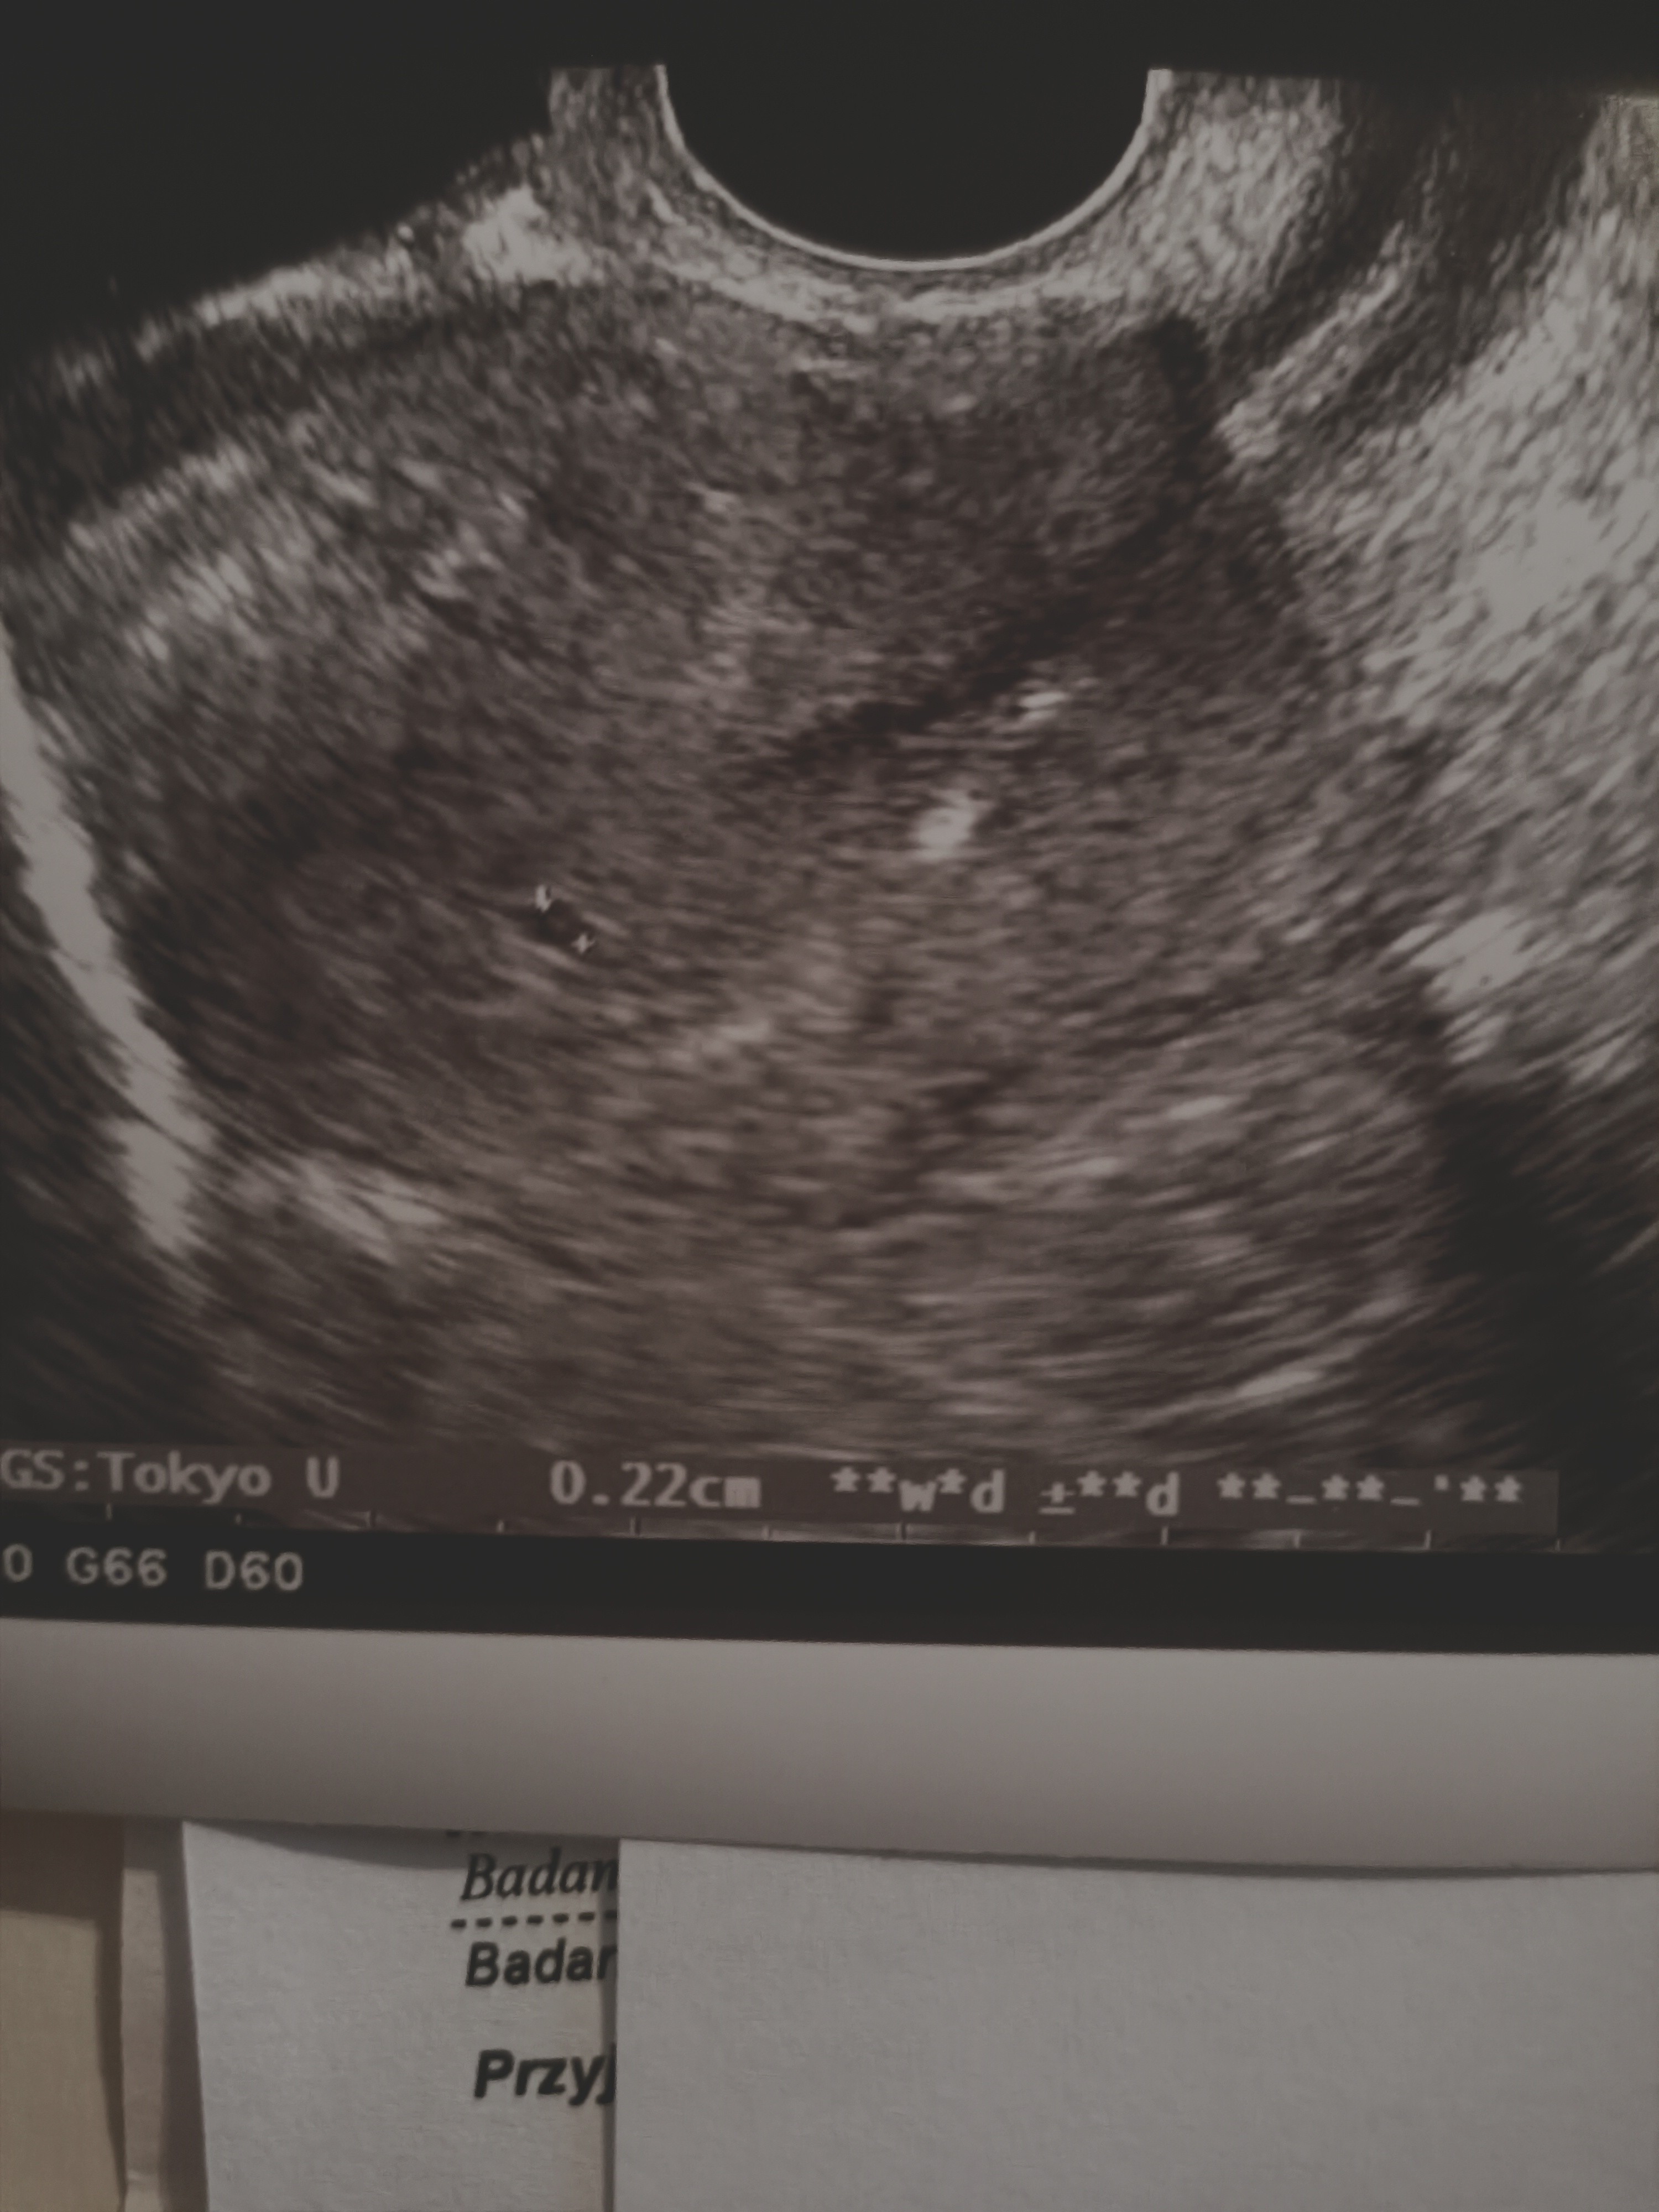

u mnie też wczoraj taka kropeczka była... U mnie termin na 12 sierpniaHejwczoraj byłam na wizycie bo okropnie bolał mnie lewy jajnik i ginekolog kazał mi przyjechać. Na szczęście wszystko dobrze. Już widać mała kropeczke a termin na 15 sierpnia

No to kropeczki już sąu mnie też wczoraj taka kropeczka była... U mnie termin na 12 sierpnia